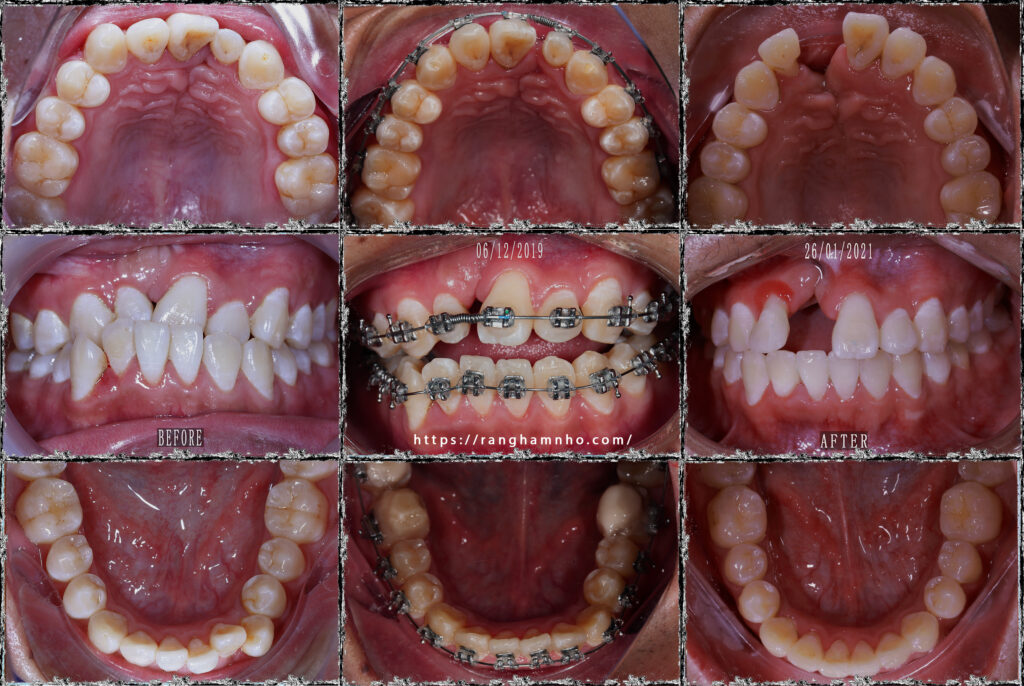

Đây là 1 case BN khe hở môi thiếu R11 bẩm sinh, trước điều trị là tình trạng hẹp hàm trên, cắn ngược hàm trên nghiêm trọng.

Bệnh nhân được giải cắn ngược, tạo khoảng phục hình R11. Kết thúc tháo niềng sau 1.5 năm điều trị